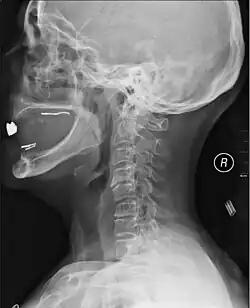

Diagnosis

A radiographic evaluation using an X-ray, CT scan, or MRI can determine if there is damage to the spinal column and where it is located.[10] X-rays are commonly available[89] and can detect instability or misalignment of the spinal column, but do not give very detailed images and can miss injuries to the spinal cord or displacement of ligaments or disks that do not have accompanying spinal column damage.[10] Thus when X-ray findings are normal but SCI is still suspected due to pain or SCI symptoms, CT or MRI scans are used.[89] CT gives greater detail than X-rays, but exposes the patient to more radiation,[91] and it still does not give images of the spinal cord or ligaments; MRI shows body structures in the greatest detail.[10] Thus it is the standard for anyone who has neurological deficits found in SCI or is thought to have an unstable spinal column injury.[92]